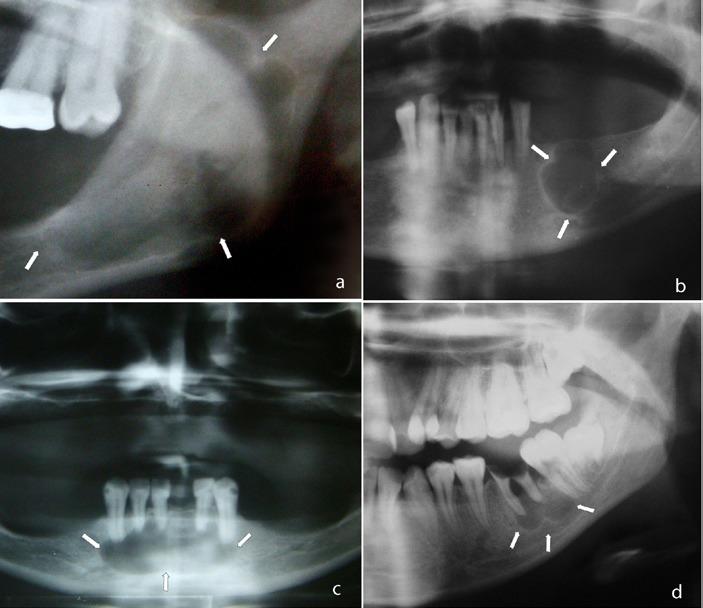

The prevalence of odontogenic and nonodontogenic cysts was 3.51%; males were affected more frequently than females. There were 452 odontogenic cysts (98.5%) and seven nonodontogenic cysts (1.5%). The most frequent odontogenic cyst was radicular (54.7%), followed by dentigerous (26.6%), residual (13.7%), odontogenic keratocyst (3.3%), and lateral periodontal cyst (0.2%). Nasopalatine duct cyst (1.5%) was the only nonodontogenic cyst. By age, cysts peaked in the third decade (24.2%). Concerning location, no statistically significant difference was found between the maxilla and mandible (p>0.05). The most frequent radiological feature of these lesions was unilocular cyst (93.7%). Pathologies associated with cystic lesions occurred in 14.7%.

牙源性和非牙源性囊肿的患病率为 3.51%;男性比女性更容易受影响。其中 452 例为牙源性囊肿(98.5%),7 例为非牙源性囊肿(1.5%)。最常见的牙源性囊肿是根端囊肿(54.7%),其次是含牙囊肿(26.6%)、残余囊肿(13.7%)、牙源性角化囊肿(3.3%)和牙周侧囊肿(0.2%)。鼻腭管囊肿(1.5%)是非牙源性囊肿中唯一的一种。按年龄划分,囊肿在 30 岁年龄段达到高峰(24.2%)。就位置而言,上颌骨和下颌骨之间无统计学差异(p>0.05)。这些病变的最常见影像学特征是单房性囊肿(93.7%)。囊性病变相关的病理发生在 14.7%的病例中。